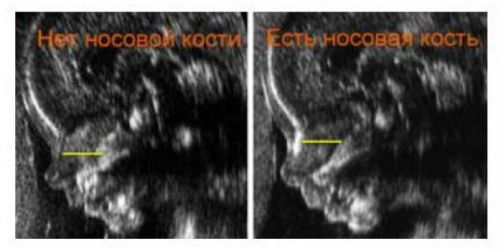

- отсутствие основной носовой кости. Дауны, как правило, имеют приплюснутую форму лица. Данный признак указывает на наличие патологии.

Симптом даунизма (отсутствие кости носа) на снимке 2-D УЗИ

- Если на УЗИ носовая кость отсутствует или меньше положенных размеров, это характерный признак синдрома Дауна.